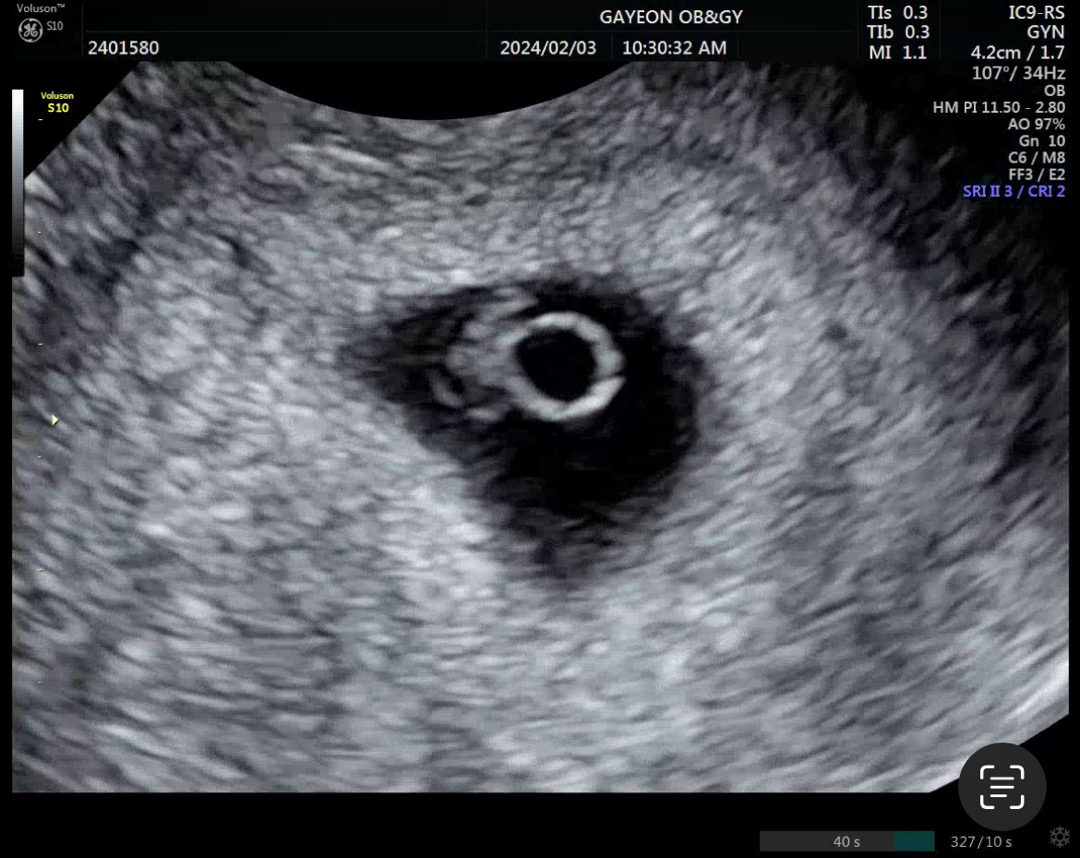

지난 토요일에 촘파+심소 듣고 왔어요 어플 주수로 6주 0일에 병원 간건데 크기 재보시고 6주 3일 이라고 하셨고요 아기는 0.65센티였오요! 병원에서 별다른 말씀이 없으시긴 했는데 잘 크고 있는건지 뒤늦게 궁금해져서요ㅠ 저 비어있는 링 같은 게 난황이고 왼쪽 젤리같은게 아기인가요???? 담주 토 병원 가는데 잘 크고 있는 거겠쥬!?!🥹

맞아요~ 난황이라는 아기 도시락 쫍쫍하면서 잘 크고 있는 거에요😀